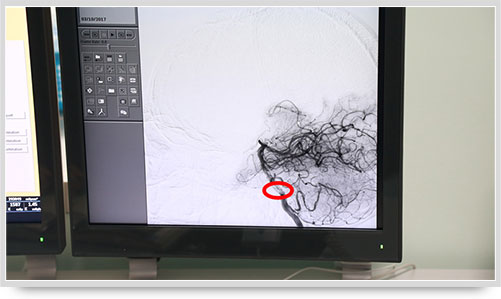

45歲的朱姓患者因“多發(fā)性腔性腦梗塞”頭暈不明,接受了全腦血管造影術(shù),術(shù)中顯示他的顱內(nèi)椎動脈血管痙攣(紅圈內(nèi)為病變部位)。據(jù)李主任介紹,以前像腦梗塞等腦血管疾病只能被定位到腦的功能區(qū)域,無法確定責(zé)任血管,而實施全腦血管造影術(shù)就能精準(zhǔn)地找出病變血管,好比揪出了造成腦梗塞的“禍?zhǔn)?rdquo;,大大提高了腦血管疾病的診治水平。

之前,另一位61歲的李姓腦出血患者,康復(fù)治療半個月后復(fù)查,也接受了全腦血管造影術(shù),術(shù)中顯示大腦前動脈A1段動脈瘤(不同維度顯影,紅圈內(nèi)為動脈瘤瘤體)。像這樣的病人,必須進(jìn)一步進(jìn)行手術(shù)治療,及早清除動脈瘤,避免因瘤體破裂造成再次出血危及生命。